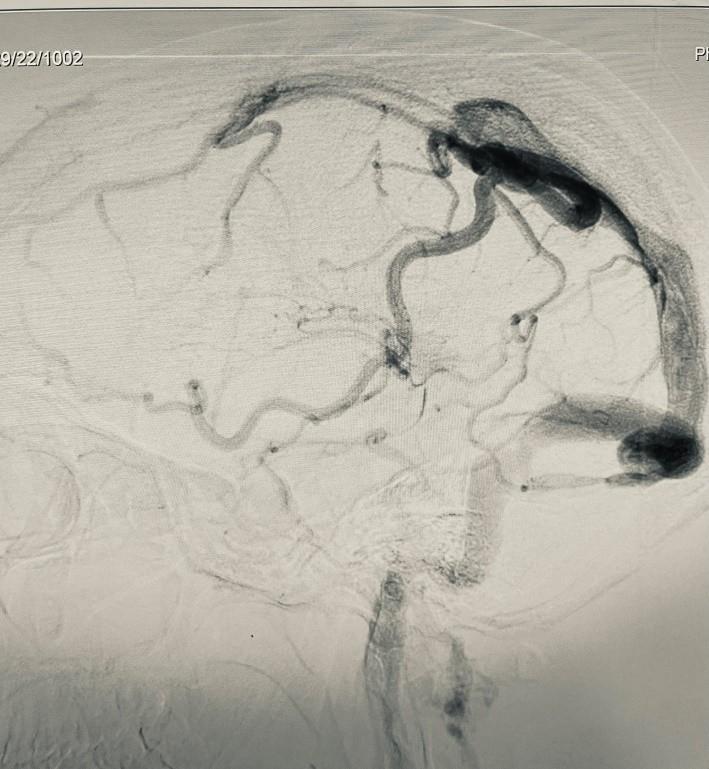

Cerebral DSA was done which showed venous congestion, Right transverse sigmoid venous junction stenosis.